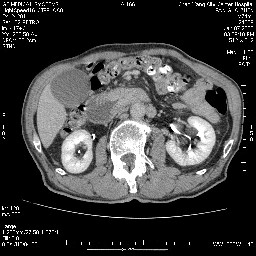

女,74岁,呕吐10余日

十二指肠降段扩张,水平段狭窄成鼠尾状,肠壁明显增厚,胰腺勾突增大成不均匀强化,其内可见低密度区,胆囊增大,1十二指肠水平段腺癌侵犯胰腺勾突可能大,2胰腺癌侵犯十二指肠(只有胆囊增大没有肝内外胆管扩张不好解释)代除外.

十二指肠降段扩张,水平段狭窄成鼠尾状,肠壁明显增厚,胰腺勾突增大成不均匀强化,其内可见低密度区,胆囊增大,1十二指肠水平段腺癌侵犯胰腺勾突可能大,2胰腺癌侵犯十二指肠 。

今日手术结果:胰腺钩突癌侵犯十二直肠,腹腔淋巴结转移.